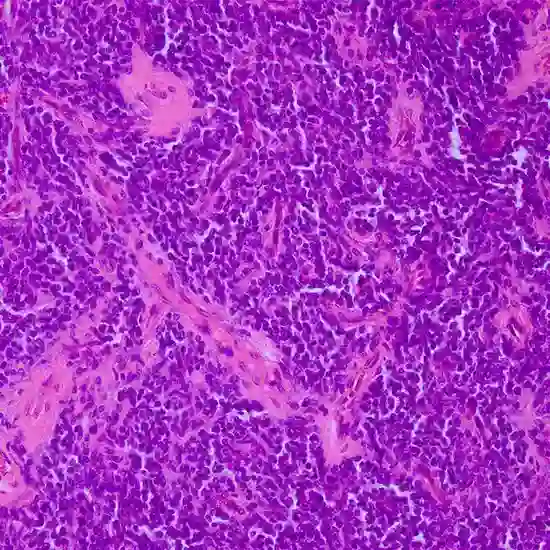

primitive neuroectodermal tumor

A primitive neuroectodermal tumor (PNET) is a type of aggressive and malignant brain tumor that arises from embryonic or primitive neural cells. PNETs are part of a family of tumors known as central nervous system (CNS) embryonal tumors, which also include medulloblastomas, pineoblastomas, and atypical teratoid/rhabdoid tumors (AT/RT).

PNETs typically occur in children and young adults, although they can occur at any age. They can arise in various parts of the central nervous system, including the brain, spinal cord, and peripheral nerves.

PNETs are characterized by their rapid growth and tendency to spread to other parts of the CNS.